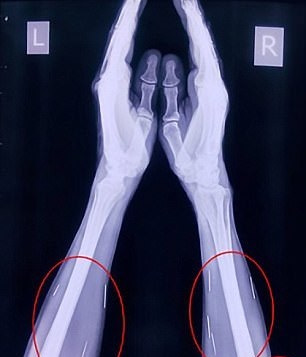

تاکنون هیچکدام از بیمارستان‌هایی که این خانواده به آنها مراجعه کرده‌اند حاضر نشده‌اند برای خارج کردن این سوزن‌ها از بدن او کاری انجام دهند. از این 70 سوزن، 40 عدد از آنها در گلو، 25 عدد در پای راست و 2 عدد نیز در دو دست او است.